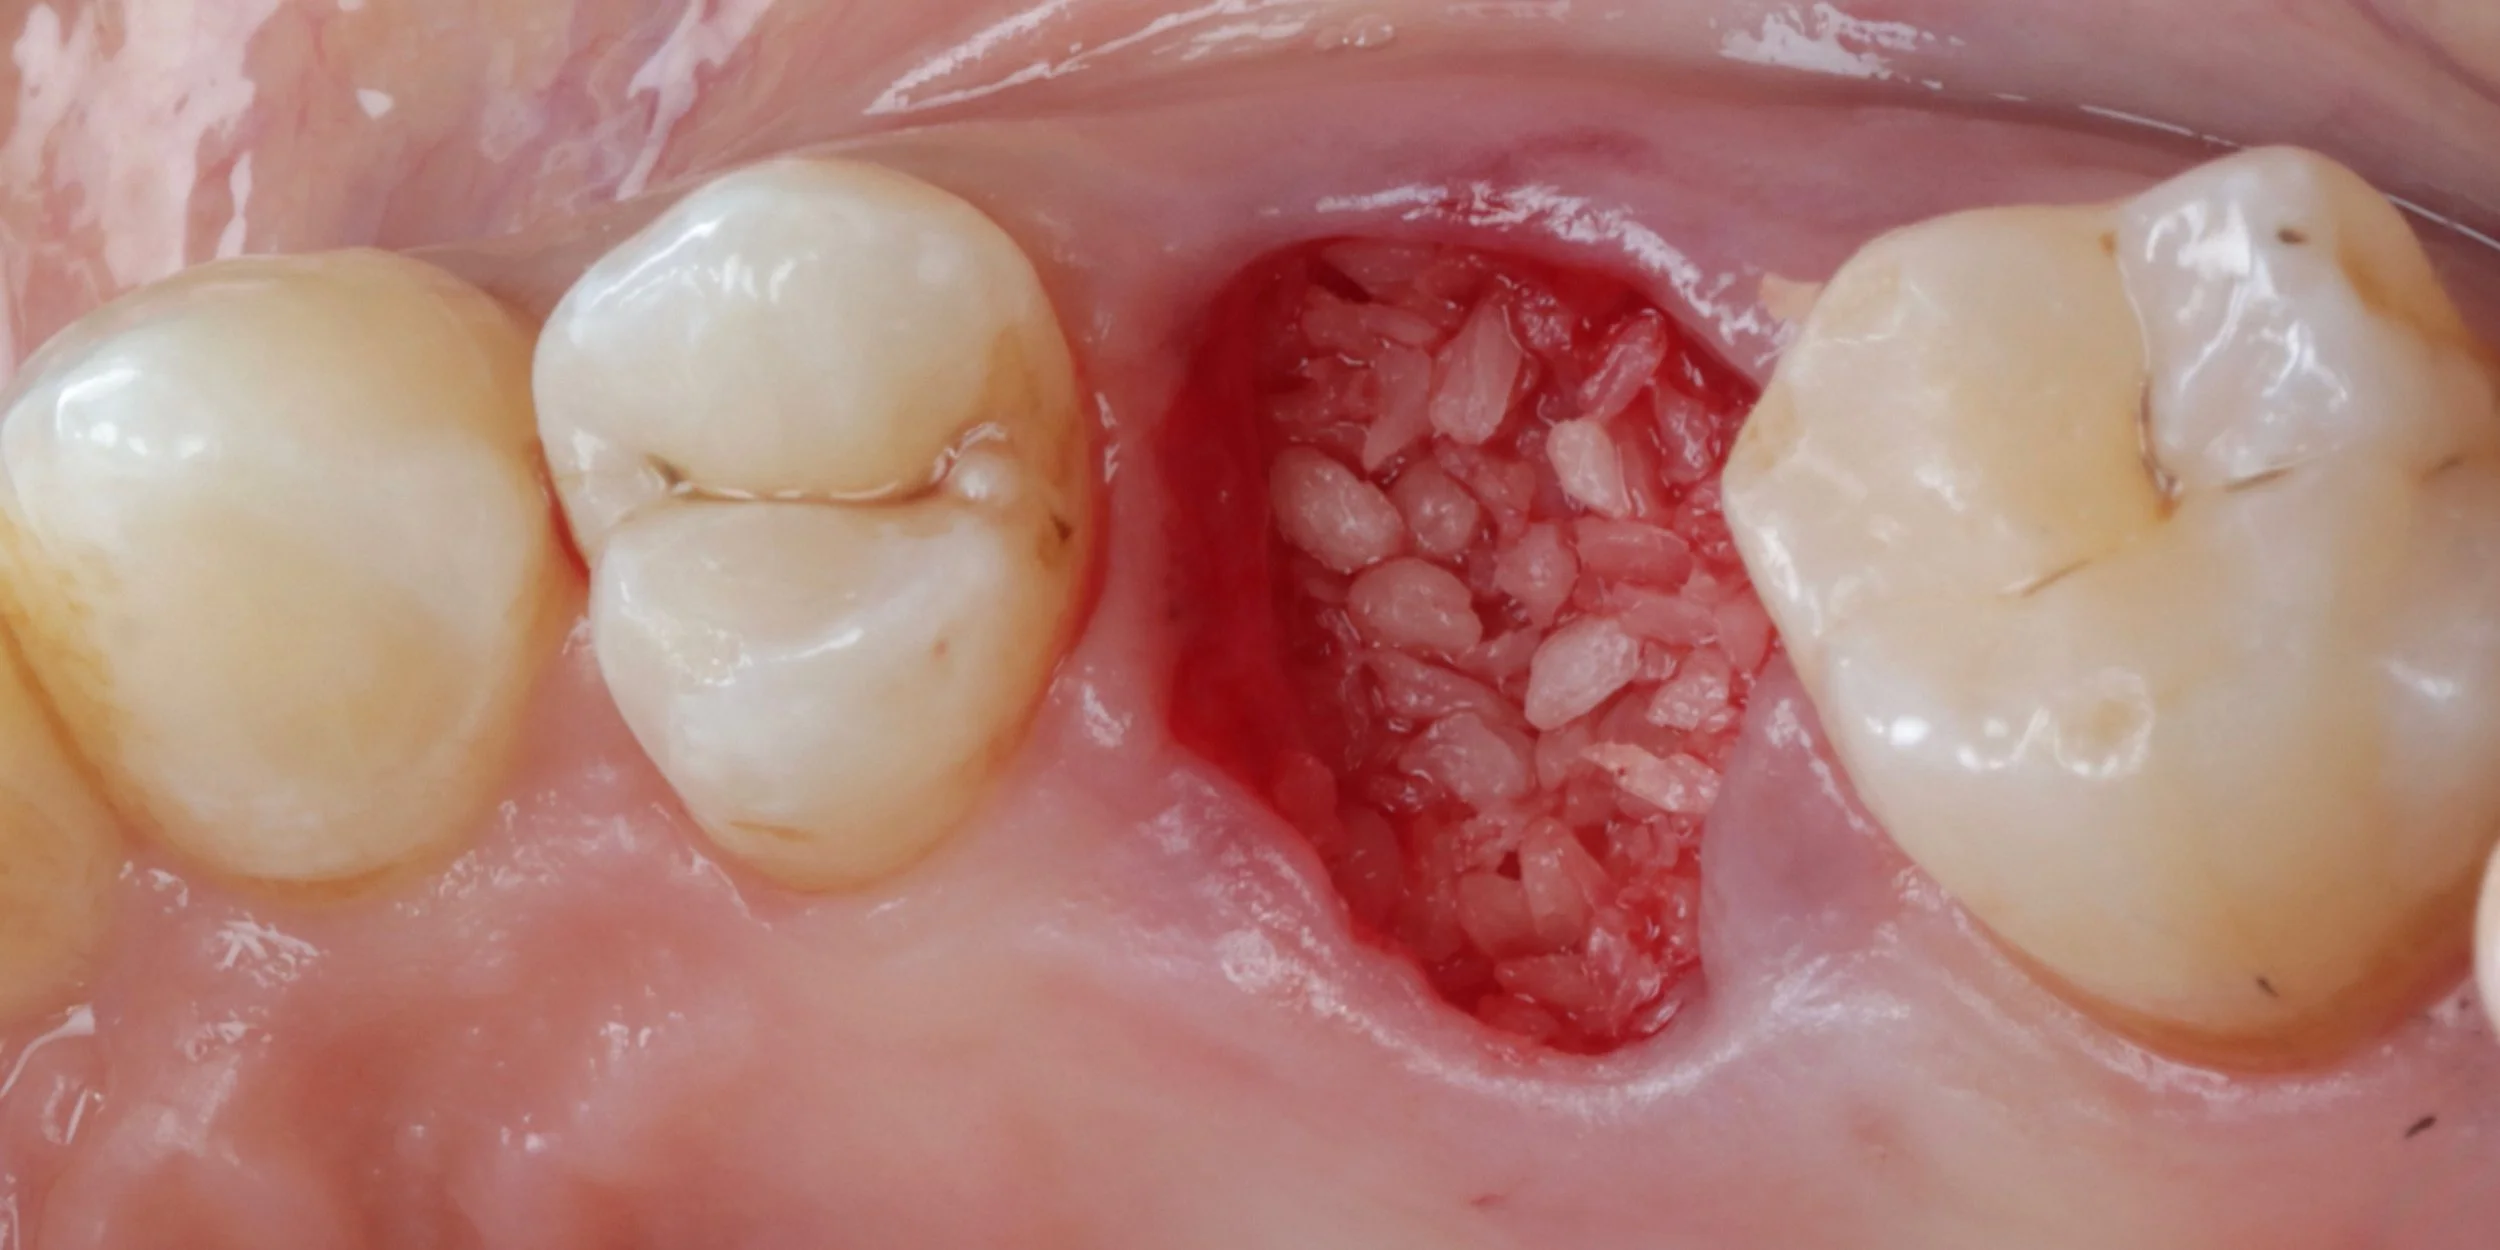

This under utilised yet highly valuable skill forms the foundations to help maintain gingival and alveolar architecture. From the general to the implant dentist, 15c will provide you with a predictable and simplified approach to ensure you can cultivate the ideal conditions for future implant or bridge placement for your patients. Learn surgical tips to improve your extraction and suturing techniques. Become confident in socket debridement and cleansing. Understand and see the different biomaterials available and the advantages and disadvantages of each. Practice how to use all of these skills to neatly and confidently perform socket preservation in practice.